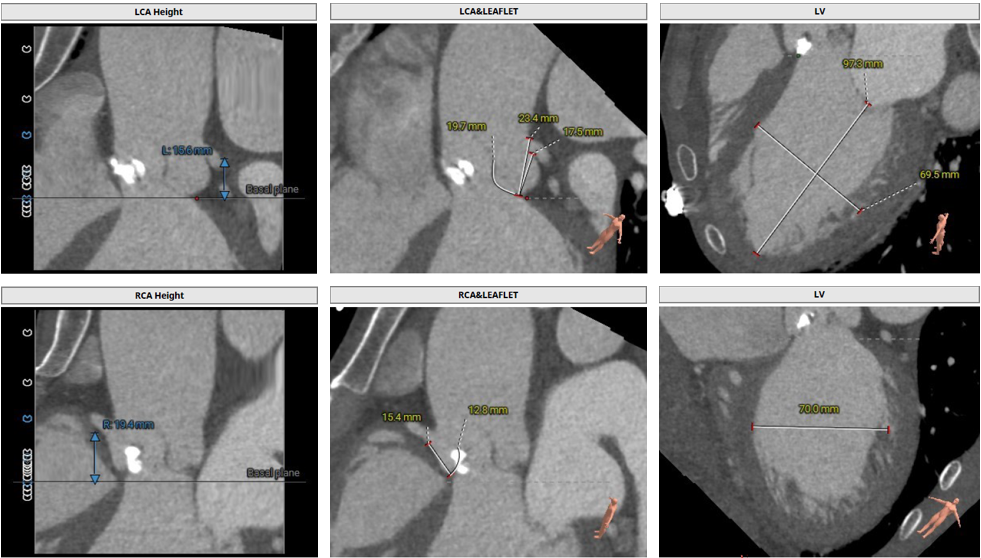

• 冠脉开口高度可,左冠瓣叶稍冗长,左冠切线位瓣叶长度>冠脉开口到瓣叶附着缘距离,右冠切线位瓣叶长度<冠脉开口到瓣叶附着缘距离。

冠脉阻挡风险评估

• 冠脉开口高度可,左冠切线位瓣叶长度>冠脉开口到瓣叶附着缘距离,结合瓦氏窦、STJ内径综合预估,冠脉风险适中,术中关注左冠血流灌注。

• 冠脉开口高度可,左右冠切线位瓣叶长度<冠脉开口到瓣叶附着缘距离。